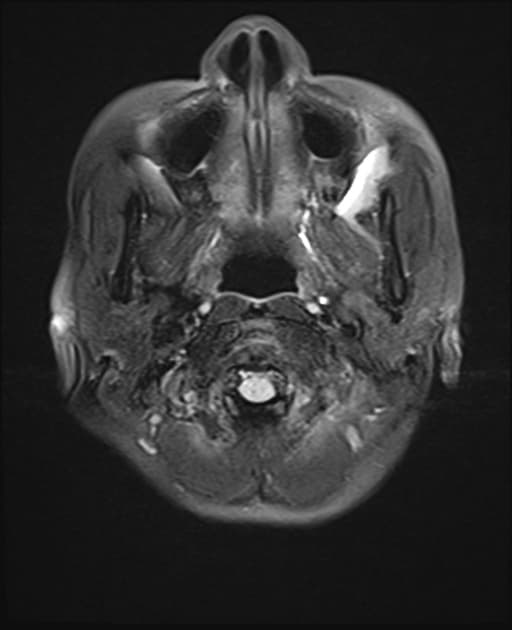

Axial T2

Temporal bone rhabdomyosarcoma with leptomeningeal metastases

Có một khối u dạng thùy, tăng quang không đồng nhất, khu trú tại ống tai ngoài, hòm nhĩ, các tế bào chũm và tai trong bên trái. Khối u có tín hiệu thấp trên các hình ảnh T1 và tín hiệu cao trên các chuỗi T2 và FLAIR. Đã ghi nhận sự xâm lấn vào góc cầu tiểu não bên trái. Có hiệu ứng khối đi kèm gây chèn ép lên não giữa, cầu não và não thất tư.

Phía trước, khối u tiếp giáp với thùy thái dương dưới. Sự xâm lấn vào phía trong dẫn đến tiếp giáp với khoang động mạch cảnh bên trái, với các khoảng trống tín hiệu dòng chảy vẫn được bảo tồn trong các mạch máu lân cận. Xâm lấn ra phía trước ngoài liên quan đến tuyến mang tai kèm theo một hạch bạch huyết tuyến mang tai lớn. Có tăng quang màng não dạng nốt dày dọc theo lều tiểu não bên trái, thân não, màng não vùng nền, vòm sọ và bán cầu tiểu não, phù hợp với lan tỏa màng não mềm.

Các khối u cạnh màng não có nguy cơ xâm lấn nội sọ và lan tỏa màng não mềm cao hơn, như đã thấy trong trường hợp này. Hình thái dạng thùy, tăng quang không đồng nhất, bao quanh mạch máu nhưng vẫn bảo tồn khoảng trống tín hiệu dòng chảy, lan truyền quanh dây thần kinh và nền sọ, liên quan hạch vùng và tăng quang màng não dạng nốt lan tỏa là những đặc điểm của bệnh giai đoạn muộn. Sự xâm lấn nội sọ vào góc cầu tiểu não và các cấu trúc hố sau, cùng với hiệu ứng khối lên thân não và não thất tư, phản ánh tính chất xâm lấn mạnh. Di căn màng não mềm ảnh hưởng đáng kể đến việc phân giai đoạn và tiên lượng, đồng thời đòi hỏi chẩn đoán hình ảnh toàn bộ trục thần kinh và quản lý ung thư đa chuyên khoa.